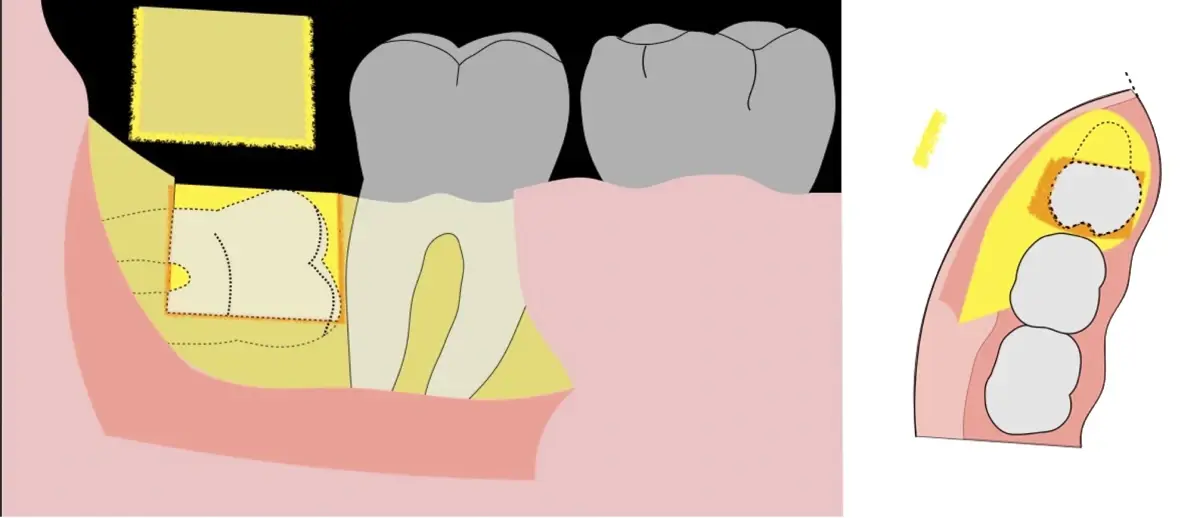

El procedimiento puede variar en su complejidad dependiendo de su ubicación, profundidad, angulación, y la densidad ósea circundante.2 Uno de los pasos más críticos y cruciales en la extracción es la osteotomía previa y concomitante al acceso quirúrgico del diente, para lo cual se utilizan diversos instrumentos como cinceles y martillos, instrumental rotatorio o de corte por ultrasonido.3

En contraste, el instrumento piezoeléctrico utiliza un corte micrométrico que retira un área de superficie mínima de hueso, y reduce el riesgo de termonecrosis marginal en comparación con las fresas rotatorias convencionales.9 Los micromovimientos mejoran la precisión en el corte y el control táctil, y eliminan las macrovibraciones que se producen con los instrumentos rotatorios.10 Su frecuencia de oscilación es la amplitud de 60-200 μm horizontalmente y de 20-60 μm en sentido vertical, lo que es muy inferior en comparación con las micro sierras oscilantes; por lo tanto, proporciona cortes de osteotomía precisos y seguros. Adicionalmente, posee vibraciones ultrasónicas que descomponen el líquido de irrigación en partículas muy pequeñas (fenómeno de cavitación, que produce un efecto hemostático y así reduce la pérdida de sangre), lo que proporciona una visión clara y sin obstáculos del campo quirúrgico11,12.